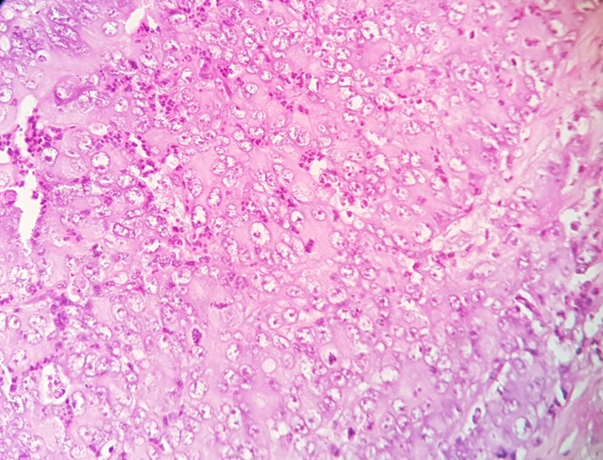

Materials and Methods: Cross sectional study was performed on 70 cases which include resected specimens of stomach, small intestine and colorectal adenocarcinoma and biopsies of esophagus and these organs. The samples were divided into Group A (Esophagus and stomach) and Group B (Small intestine and colorectal). The samples were grossed and processed in the pathology department, and sections were stained with hematoxylin and eosin stain for histopathological confirmation of malignancy and graded as well-differentiated (gradeI), moderately-differentiated (grade II) and poorly-differentiated (gradeIII ) adenocarcinomas. The confirmed samples were processed for immunomarker study of HER2/ neu.

The specimens were subjected to a thorough gross examination. Appropriate sections were taken. The sections were processed and paraffin blocks were prepared. The sections were cut at 4-5 micron thickness and stained with hematoxylin and eosin for histopathological confirmation of malignancy. The histological grading of these tumors was done as well-differentiated (I), moderately differentiated (II), and poorly-differentiated (III) according to the criterion of the American Joint Committee on Cancer. The confirmed malignant specimens and biopsies were processed for immunomarker study of HER2/ neu. Known positive breast cancer cases were used as positive controls, with the omission of primary antibodies for the negative control. For immunohistochemical staining by HER2/ neu, m onoclonal antibody of C-erbB-2 gene product was used (clone TAB250), supplied in a liquid form ready to use.

The Immunohistochemistry slides were scored according to scoring system by Hoffman et al.[9] No staining or membrane staining in < 10% tumor cells ,were labelled as score “0” and considered negative for HER2/neu overexpression. Faint/barely perceptible membranous staining in ≥ 10% of tumors cells were labelled as score “1” and considered negative. Weak to moderate complete, basolateral or lateral membranous staining in ≥ 10% tumor cells were labelled as score “2” and considered equivocal. Strong complete, basolateral or lateral membranous staining in ≥ 10% of tumors cells were labelled as score “3” and considered positive.